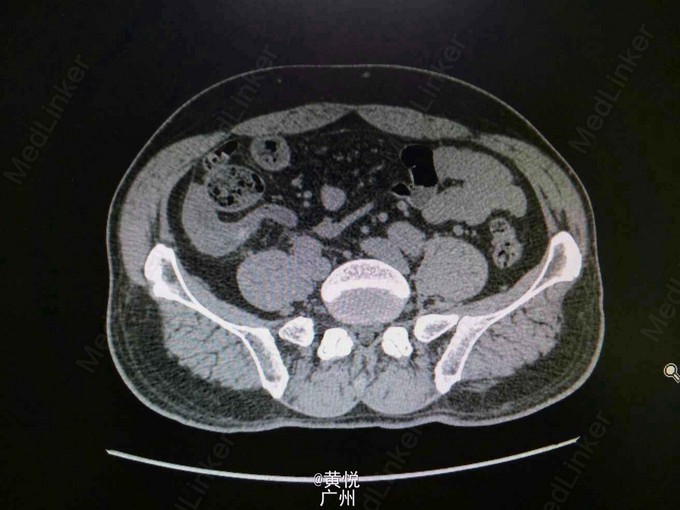

查体:生命体征平稳,屈曲体位,心肺无特殊,腹平软,右下腹麦氏点有压痛以及反跳痛,无腹部包块,双肾叩击痛(—)。辅助检查:血常规提示WBC 1.3*10^9;中性粒细胞 6.7*10^9,中性粒细胞比值正常;血生化未见异常。腹平片提示:小肠少许积气,考虑肠郁张;腹部CT检查提示结肠局部肠壁增厚并周围淋巴结增大,建议进一步检查,考虑右肾囊肿。